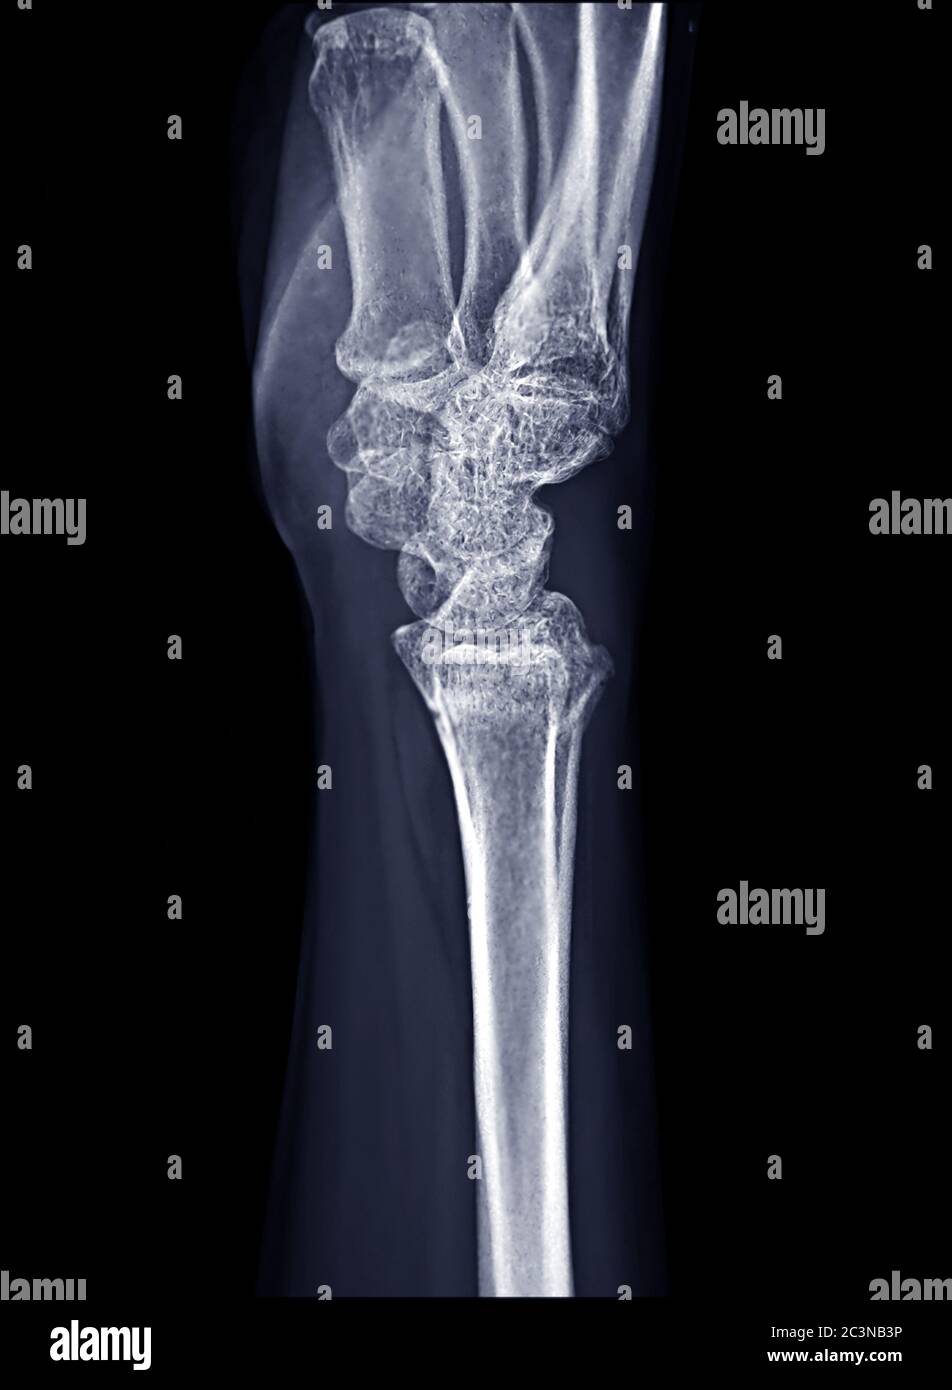

Xray image of wrist joint for diagnosis rheumatoid arthritis Stock Photo Alamy Arthritis Diagnosis X Ray   when diagnosing arthritis, your doctor will likely do a complete physical examination of your entire body, including your spine, joints,. Other imaging tests may also be done. A doctor may also use an mri or ultrasound scan ,.   diagnosis is based on a combination of clinical, radiographic, and serological criteria. For this reason, radiologists at hospital for special. Arthritis Diagnosis X Ray.

Xray image of Right wrist joint Lateral view for diagnosis rheumatoid arthritis Stock Photo Alamy Arthritis Diagnosis X Ray   when diagnosing arthritis, your doctor will likely do a complete physical examination of your entire body, including your spine, joints,.   diagnosis is based on a combination of clinical, radiographic, and serological criteria. For this reason, radiologists at hospital for special surgery often. Other imaging tests may also be done. A doctor may also use an mri or ultrasound. Arthritis Diagnosis X Ray.